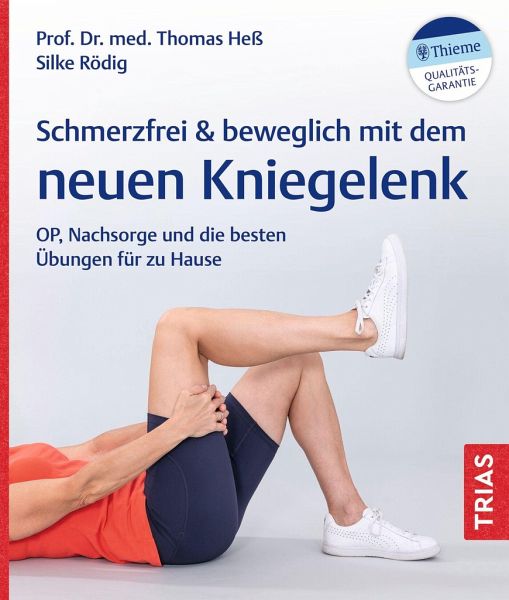

Schmerzfrei & beweglich mit dem neuen Kniegelenk

OP, Nachsorge und die besten Übungen für zu Hause

Knie ohne Schmerzen

Bei Arthrose im Knie kann ein künstliches Kniegelenk die Lösung sein, um wieder beschwerdefrei gehen zu können. Doch viele haben Angst vor einer Knie OP, auch wenn ihre Gonarthrose große Schmerzen verursacht. Diese Angst wollen die Autoren Ihnen nehmen:

- Ihre Knie in guten Händen: Prof. Dr. Thomas Heß, Spezialist für Knie OPs, und Silke Rödig, Physiotherapeutin in einer Rehaklinik, stehen für Kompetenz rund um Ihre Knieprobleme.

- Gut vorbereitet in die OP: Alle wichtigen Hintergründe über Arthrose, künstliche Gelenke und den Eingriff.

- So werden Sie schnell wieder fit: Schmerzlindernde Nachsorge und die besten Übungen nach der Knie OP für zu Hause.

Endlich wieder schmerzfrei laufen!

Bei Arthrose im Knie kann ein künstliches Kniegelenk die Lösung sein, um wieder beschwerdefrei gehen zu können. Doch viele haben Angst vor einer Knie OP, auch wenn ihre Gonarthrose große Schmerzen verursacht. Diese Angst wollen die Autoren Ihnen nehmen:

- Ihre Knie in guten Händen: Prof. Dr. Thomas Heß, Spezialist für Knie OPs, und Silke Rödig, Physiotherapeutin in einer Rehaklinik, stehen für Kompetenz rund um Ihre Knieprobleme.

- Gut vorbereitet in die OP: Alle wichtigen Hintergründe über Arthrose, künstliche Gelenke und den Eingriff.

- So werden Sie schnell wieder fit: Schmerzlindernde Nachsorge und die besten Übungen nach der Knie OP für zu Hause.

Endlich wieder schmerzfrei laufen!